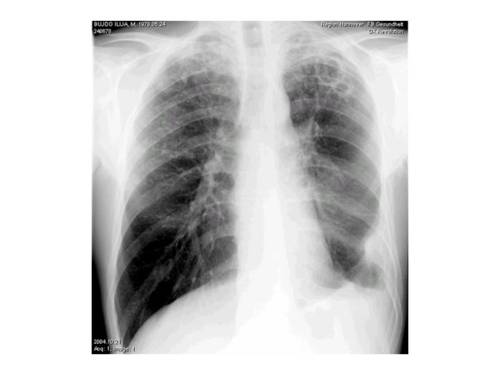

- Röntgenuntersuchung der Lunge